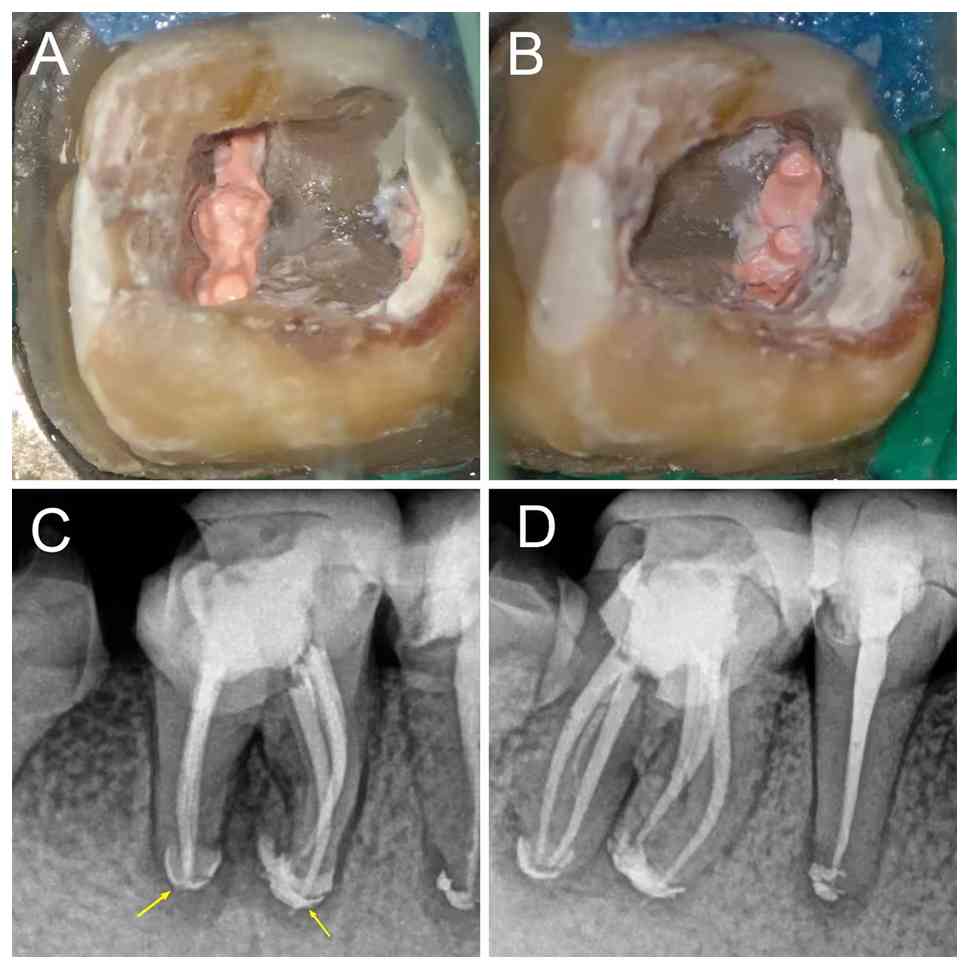

Post-obturation clinical and

radiographic assessment (November 2023). (A) Pulp chamber view of

three obturated (A) mesial and (B) distal root canals. (C)

Post-obturation periapical radiograph (straight orthogonal view)

taken in November 2023. Arrows indicate high-density filling

material extruding beyond the apex. (D) Post-obturation periapical

radiograph (mesio-oblique view).

Figure 2

Post-obturation clinical and radiographic assessment (November 2023). (A) Pulp chamber view of three obturated (A) mesial and (B) distal root canals. (C) Post-obturation periapical radiograph (straight orthogonal view) taken in November 2023. Arrows indicate high-density filling material extruding beyond the apex. (D) Post-obturation periapical radiograph (mesio-oblique view).

At the 10-day follow-up, the patient reported improvement, experiencing no discomfort in the affected tooth. Vertical percussion of tooth no. 46 elicited no pain and the sinus tract had resolved. The tooth was isolated with a rubber dam and the root canal was rinsed using 20 ml 3% NaClO and ultrasonic activation before being obturated with the ‘continuous wave of condensation’ technique (24) using gutta-percha and iRoot SP bioceramic sealer (Innovative BioCeramix, Inc.; Fig. 2A and B). The root canal orifices were sealed with Filtek™ Z350 XT flowable composite resin (3M ESPE; 3M Deutschland GmbH), and the crown was restored using Filtek™ P60 composite resin (3M ESPE; 3M Deutschland GmbH). Postoperative multi-angle radiographs confirmed the correct placement of the gutta-percha cones. Notably, some iRoot SP paste extruded from the apical foramen to ensure maximal sealing (Fig. 2C and D). After completing the root canal treatment, the patient was referred to the Department of Prosthodontics at Chengdu Third People's Hospital (Sichuan, China) for the fabrication of a full ceramic crown to protect tooth no. 46. At the 6 month follow-up (June 2024), the patient reported no discomfort with the treated tooth no. 46. Clinical examination revealed healthy surrounding gingiva without redness or swelling, a negative percussion response and normal periodontal probing depths. Furthermore, X-ray images exhibited a successful non-surgical root canal treatment, with a visible decrease in the dark shadow surrounding the furcation and root apex. A residual high-density radiopaque area corresponding to the extruded sealer was observed (Fig. 3). At 24 month follow-up in November 2025, the patient remained asymptomatic. Multi-angle radiographic evaluation revealed complete resolution of the periapical and furcation radiolucencies, with a decrease in the extent of the extraradicular high-density area (Fig. 4A and B). Thus, continuous follow-up every 6-12 months with the patient is important; if the patient experiences unresolved periapical inflammation or recurrent discomfort, apical surgery may be considered.